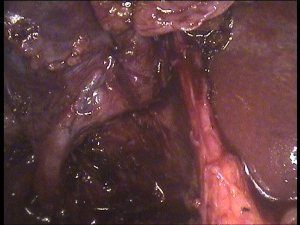

Lap chole in a 30 years old male (a surgeon himself, assistant professor, GSMedical college). Turned out to have a rather prominent accessory bile duct arising from the middle of the liver bed and draining directly into the gall bladder. After much deliberation and hesitation, this was doubly clipped and divided. Concerned at the prominent size of this duct though. Postoperative OK so far.